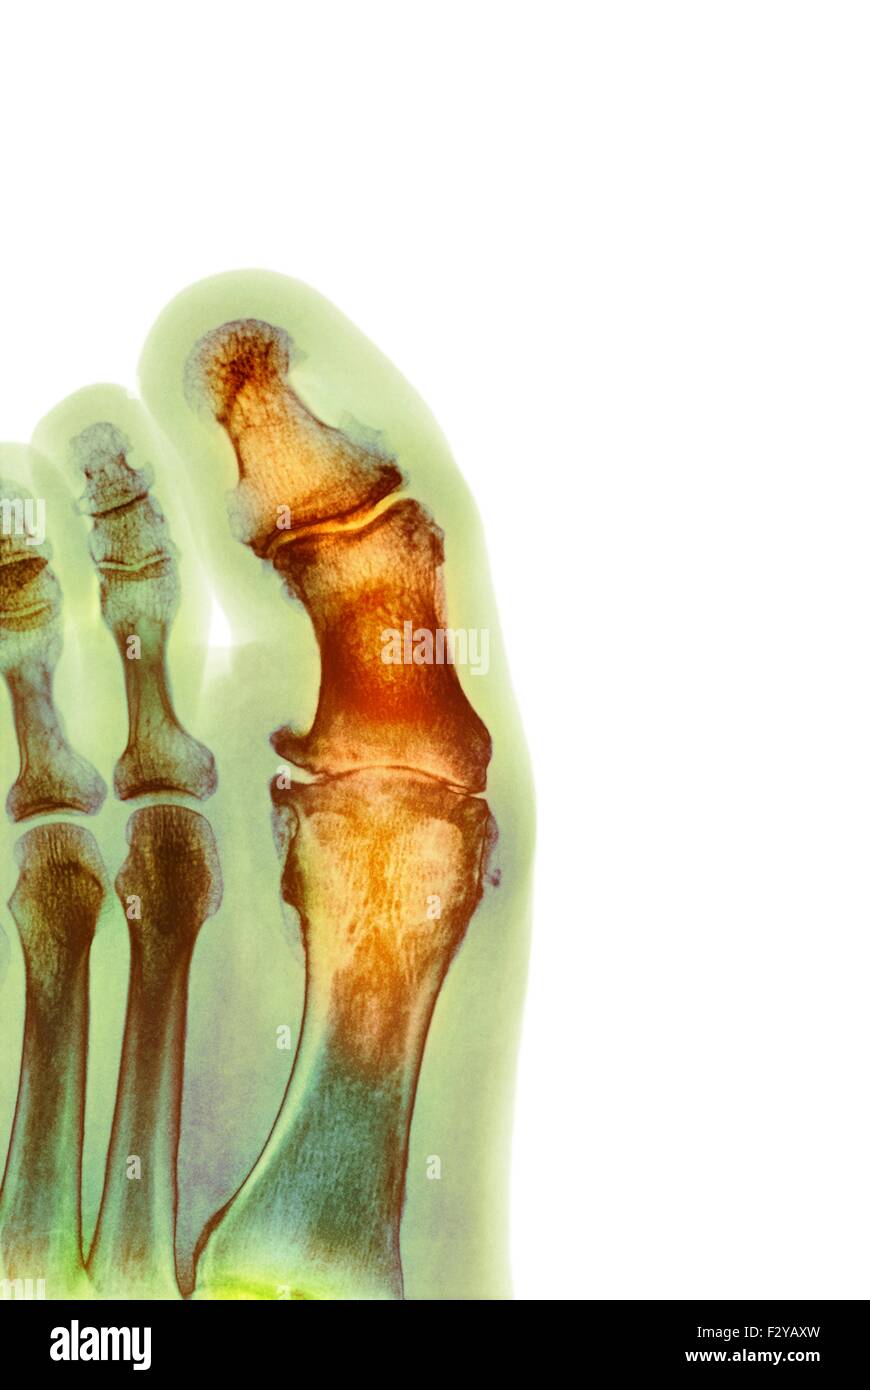

From www.sciencephoto.com

Degenerative foot deformation, Xray Stock Image F012/1378 Foot Degenerative Joint Disease osteoarthritis is a degenerative disease that worsens over time, often resulting in chronic pain. Doctors also call it degenerative joint. Joint pain and stiffness can become. It happens when the cartilage that lines your joints is worn down or damaged. osteoarthritis is a degenerative joint disease. to get pictures of the affected joint, your doctor might recommend:. Foot Degenerative Joint Disease.